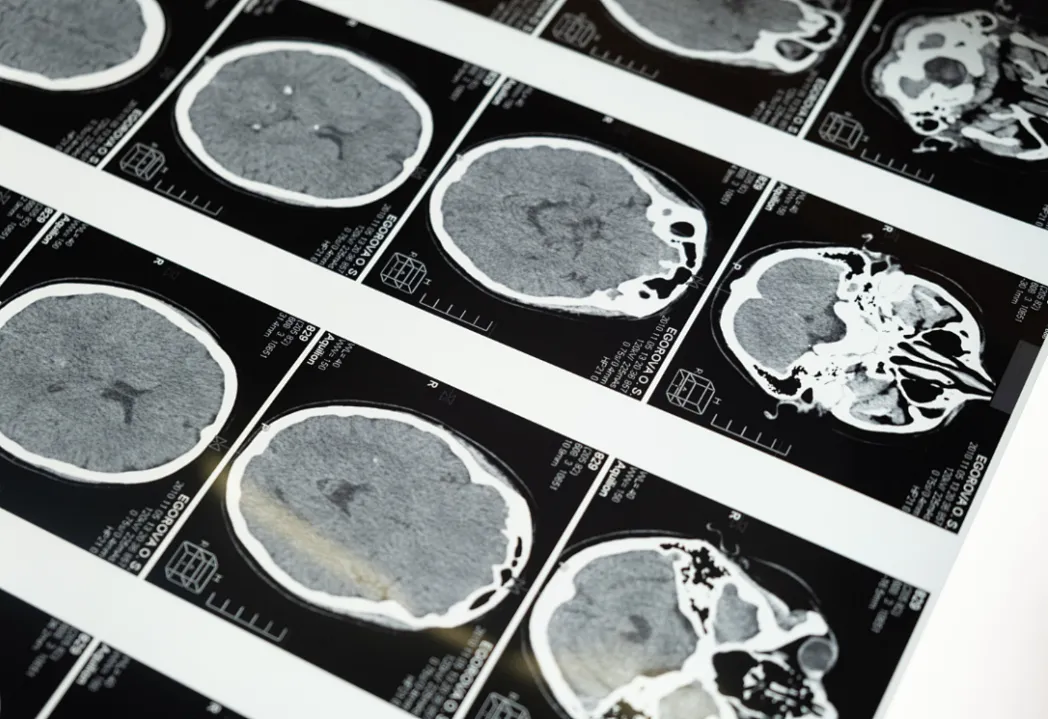

“每多做一次CT,患癌风险增加43%”的传言让许多家长忧心忡忡。然而,深圳市第二人民医院医学影像科主任李顶夫表示:“CT检查不会增加患癌风险。”这一结论基于大量科学研究和临床实践。

CT检查确实会产生一定量的辐射。根据国际原子能机构的规定,正常人每年接受的辐射总量不应超过20mSv。而常见的CT检查辐射剂量如下:颅脑CT约为1.4mSv,肺部CT约为3.5mSv,全腹部CT约为5mSv。这意味着,根据需要,正常人每年做2-5次CT检查是安全的。

对于儿童这一特殊群体,确实需要特别关注。儿童对辐射的敏感性可能是成人的2-3倍。然而,这并不意味着应该完全避免CT检查。在联合国原子辐射效应科学委员会2018年的报告中,全球CT检查占医疗照射总频度的比例为9.0%,但其对集体有效剂量的贡献却高达52.5%。这说明CT检查在临床诊断中的重要性。